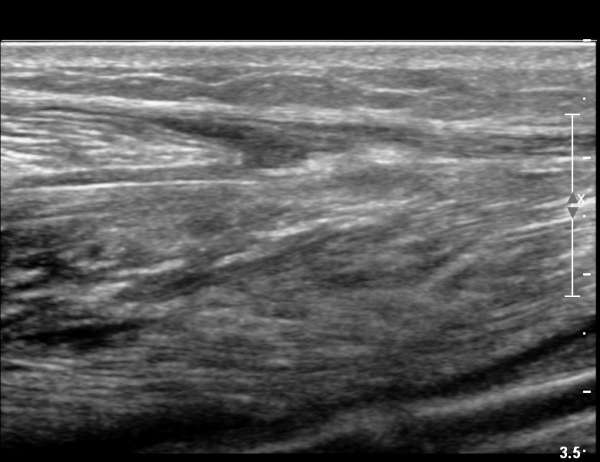

¾ÆÅ³·¹½º°Ç ±ÙÀ§ºÎ Á¾´Ü¸é°Ë»ç¿¡¼­ ¾ÆÅ³·¹½º°ÇÀÇ Àú¿¡ÄÚºÎÁ¾, ±¹¼ÒÀû ¿¬°á¼º ¼Ò½ÇÀÌ °üÂûµÇ¾î

ÆÄ¿­ÀÌ ±¤¹üÀ§ ÇÑ °ÍÀ» º¸¿©ÁÜ(»çÁø 6, 7).